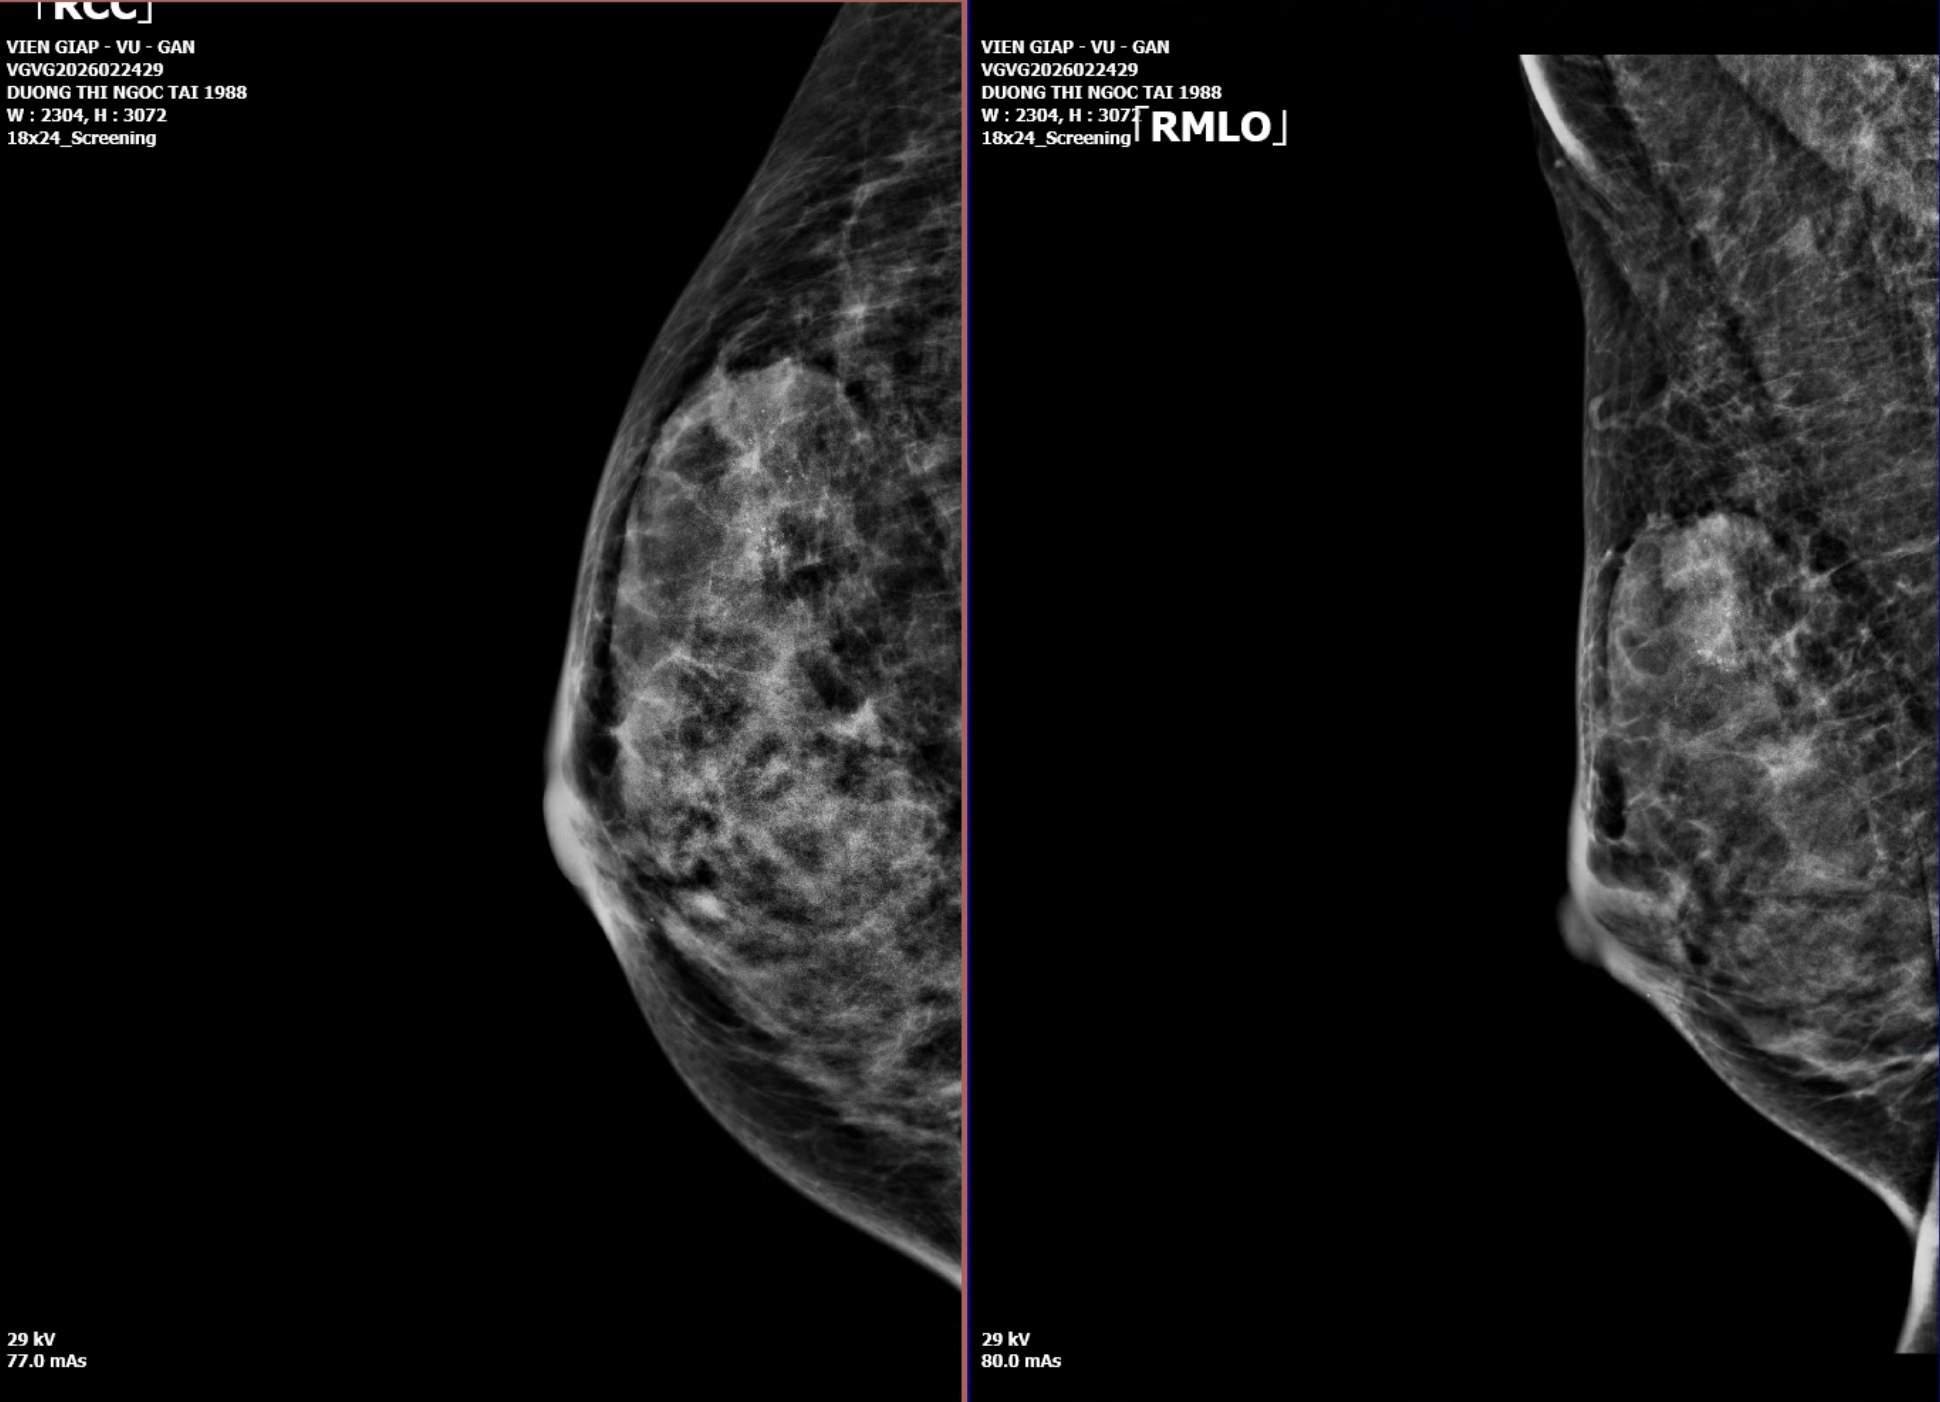

Kết quả chẩn đoán hình ảnh: Dấu hiệu cảnh báo cao

Siêu âm tuyến vú phải

- Vị trí: 1/4 trên ngoài (9–11h)

- Kích thước: 33 x 20 mm

- Đặc điểm:

- Khối đậm độ cao

- Bờ tua gai (spiculated)

- Xâm lấn mô mỡ

- Nhiều vi vôi hóa đa hình

- Tăng sinh mạch nội khối

👉 Phân loại: BI-RADS 5 (nguy cơ ác tính >95%)

BI-RADS 5 gần như bắt buộc sinh thiết ngay để xác nhận mô học.